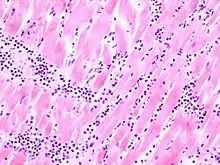

Acute myocardial infarction

Der Myokardinfarkt muss mind. 6 - 12 Stunden überlebt werden, bevor er morphologisch sichtbar wird!

Mikro: Koagulationsnekrose, Einblutungen. Die Myozyten zeigen eine verstärkte Eosinophilie und Kontraktionsbanden quer durch die Herzmuskelfasern. Typische Zellparameter wie Querstreifung, Zellkerne und Zellgrenzen gehen verloren. Das Infarktareal wird von einer Hyperämischen/hämorrhagischen Randzone begrenzt. Im Verlauf zunehmende leukozytäre Demarkation und Phagozytose des nekrotischen Gewebes, sowie Einwanderung von Fibroblasten mit Ausbildung eines narbigen Ersatzgewebes.

Makro: Lehmfarbene Abblassung mit hyperämischem/hämorrhagischem Randsaum.

![]() Akuter Myokardinfarkt, H&E. |